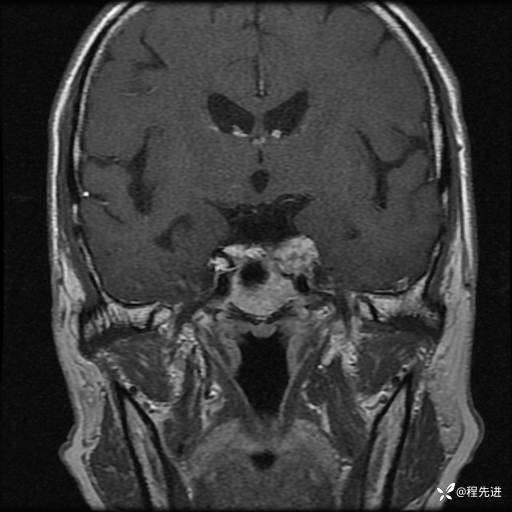

MRI平扫+增强:

T1:

T2:

T1增强: